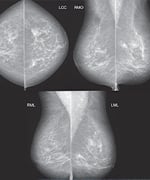

An ideal approach to treating advanced cancers would accomplish two things: 1. Eliminate the original tumor. 2. Empower the immune system to destroy the cancer cells. Then, instead of having to locate and treat every infiltrated lymph node and every hidden metastasis, the body's natural tumor surveillance system would do its work, root out the cancer, and prevent recurrence. This is the central principle behind laser-assisted immunotherapy.4,5 Laser-assisted immunotherapy involves no surgery, chemotherapy, or dangerous radiation. Instead, the technique uses a precise laser beam to destroy the primary tumor, and then delivers a powerful boost to the immune system's natural cancer defense systems.4 In this way, the entire immune system joins the fight against an individual's own specific cancer.6 Laser-assisted immunotherapy includes the following three components: 1. A laser beam operating in the "near-infrared" frequency of light.7 This beam heats tissue to a depth of several centimeters, allowing the beam to penetrate directly into a solid tumor with minimal damage to normal tissue.8 Because it can be focused directly through intact skin, no surgical incision is required. These lasers have been in use in cancer therapy for more than 20 years.9 On their own, however, they can't safely raise the temperature of tumor cells without damaging adjacent healthy tissue.9,10 That requires the use of a second component… 2. A photosensitizer, a chemical that makes cancer cells more vulnerable to destruction by the laser without the unacceptable heating of nearby normal cells.6 The technique was proven in pre-clinical studies with the use of a compound called indocyanin green (ICG) as the photosensitizer. Like the laser, ICG is safe for clinical applications and is FDA approved. The combination of the laser and photosensitizer leads to localized destruction of tumor cells. However, these two components alone may not be effective at completely ridding the body of cancer because they cannot attack distant, often hidden tumor metastases.11 To kill those, one more crucial component is required… 3. An immune system booster12, or "adjuvant," that activates the cancer patient's natural cancer-attacking killer cells.7 Growing tumors have multiple ways of evading the immune system, effectively concealing their abnormal nature from circulating immune surveillance cells. Once the tumor is partially broken up by the laser, however, the injection of the adjuvant then calls the immune system's attention to the newly revealed tumor markers.8,13 Circulating immune cells can then begin killing malignant cells anywhere they have spread in the body.14 This immune booster may soon be submitted to FDA for approval and those involved in submitting the New Drug Application have asked that we not disclose its name in print. Cancer Cell The key aspect of this approach is that the stimulated immune system attacks not only the primary tumor, but also metastases located anywhere in the body.4,6,15 Because those metastases often bear the same abnormal signal proteins as the primary tumor, they now essentially have a mark on their back for the body's natural defense mechanism to seek out and destroy—no matter where they've moved to in the body. As an added bonus, the immune system "remembers" the identifying markers of the cancer and continuously maintains surveillance to prevent future recurrence.16 In essence, laser-assisted immunotherapy creates a tiny "vaccine factory" within the victim's body that throws the entire immune system's resources at precisely that person's own tumor (see Sidebar at the end of this article for more on this topic).14 What You Need to Know Breast Cancer Mammography Advanced Breast Cancer Treatment: Hope Is On The Horizon

One year and nine months after the treatment, this patient received the following mammography report: "The result of your breast imaging exam shows no evidence of cancer."